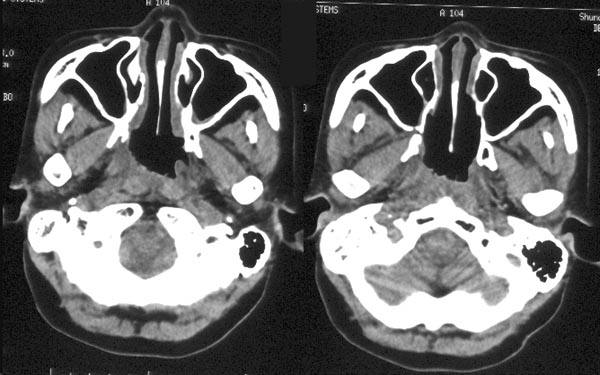

CCTV名家访谈专家张全安教授表示:鼻咽癌检查手段包括间接鼻咽镜检查,鼻咽纤维镜检查、鼻咽部CT检查和MRI检查。病理检查是确诊鼻咽癌的最重要依据。CT可以把鼻咽癌给查出来,但是在拍片的过程中病灶如果被遮挡的话,CT就不可以把鼻咽癌诊断出来,所以说CT只是有可能会发现疑似病灶。